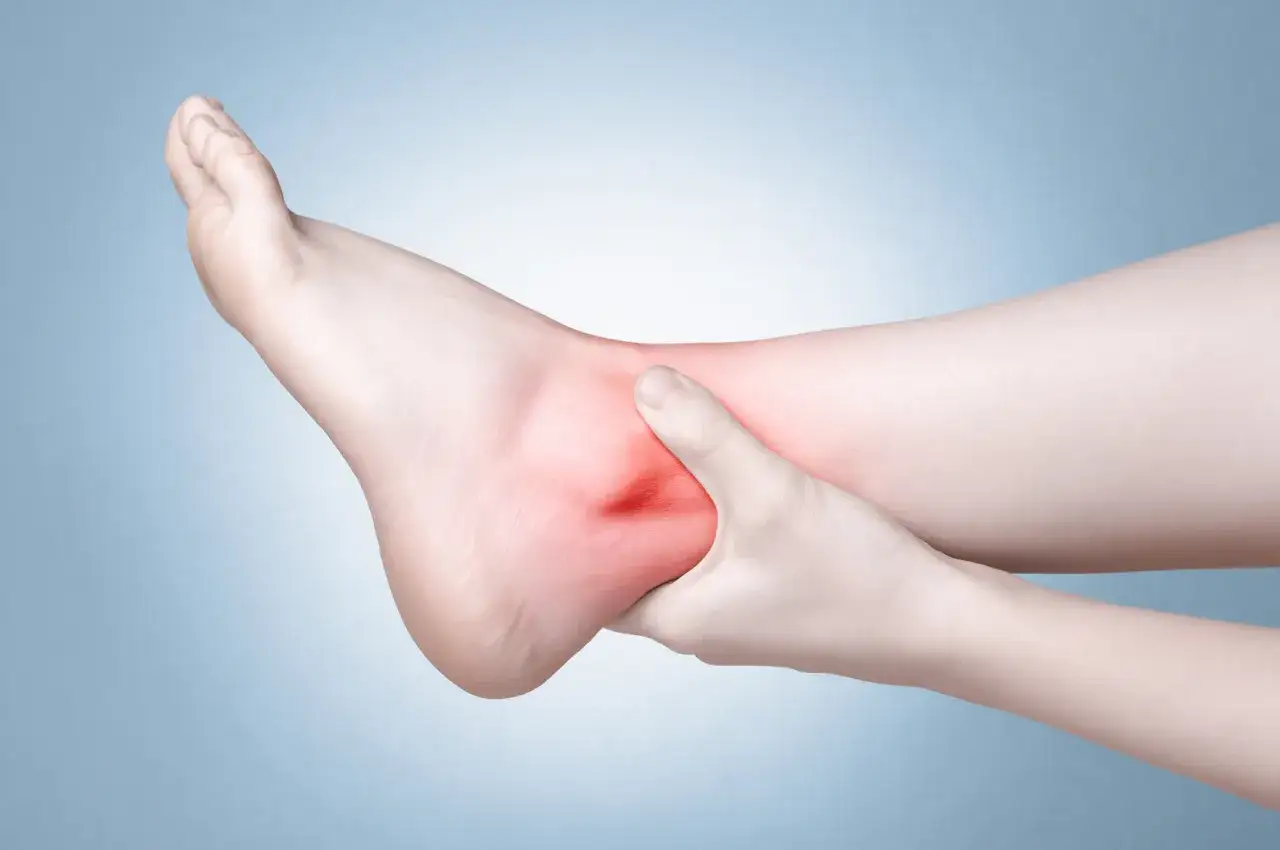

Skręcona kostka to powszechny uraz, który może dotknąć każdego z nas, niezależnie od wieku czy aktywności fizycznej. Wielu ludzi zastanawia się, jak długo trwa ból związany z tym urazem oraz jakie są objawy, które mogą się z nim wiązać. Czas trwania bólu zależy od stopnia uszkodzenia, który może być różny, od lekkiego skręcenia po poważne urazy wymagające długotrwałej rehabilitacji.

Jakie są najczęstsze objawy skręcenia kostki? Zrozumienie urazu

Rozpoznanie objawów skręcenia kostki jest kluczowe dla szybkiej diagnozy i skutecznego leczenia. Objawy skręcenia kostki mogą się różnić w zależności od stopnia urazu, ale ogólnie obejmują ból, obrzęk oraz zasinienie. Wczesne zidentyfikowanie tych symptomów pozwala na podjęcie odpowiednich kroków w celu leczenia.

Każdy stopień skręcenia kostki ma swoje charakterystyczne objawy, które mogą pomóc w diagnozie. Skręcenie I stopnia objawia się lekkim bólem oraz minimalnym obrzękiem. W przypadku skręcenia II stopnia, ból jest znacznie silniejszy, a obrzęk bardziej widoczny. Osoby z tym urazem mogą mieć trudności z poruszaniem się, ale nadal są w stanie stawać na nodze.

Natomiast w skręceniu III stopnia, objawy są najbardziej dramatyczne. Pacjenci często doświadczają intensywnego bólu, znacznego obrzęku oraz niemożności obciążania stawu. Zrozumienie tych różnic jest kluczowe dla podjęcia odpowiednich działań w przypadku skręcenia kostki.